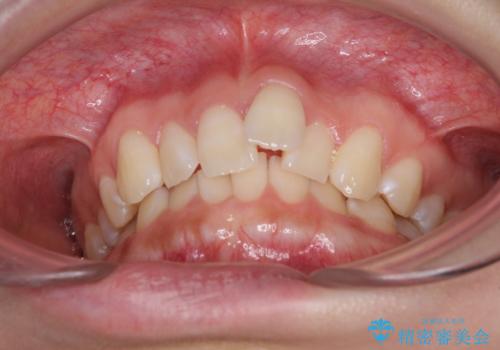

前歯のデコボコを治したい インビザライン矯正治療

- 前歯のデコボコ気になるとのことで来院された患者様です。

下顎骨が上顎骨に対して右側にシフトしており、さらに下顎が後方に位置しているため、非常に強い咬合力で食いしばっている状態でした。

上下顎ともに歯列全体の後方移動とIPR(歯と歯の間を削る)によってデコボコが解消するように設計し、インビザラインにより治療を行うこととしました。